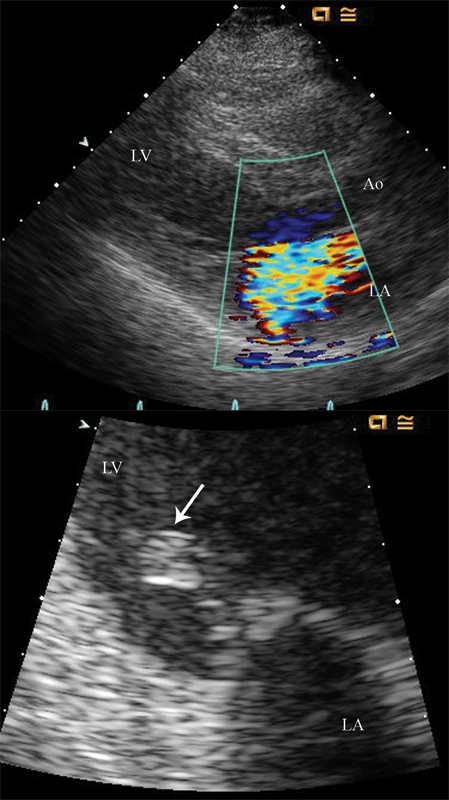

فحوصات تشخيصية لبعض امراض القلب والشرايين التاجية